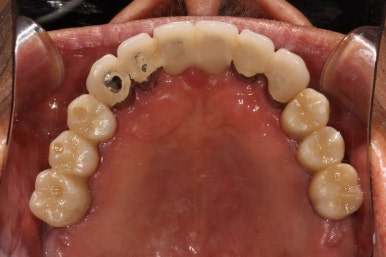

왼쪽: 위턱 교합면, 오른쪽: 아래턱 교합면

처음 치과에 방문하시면, 어떤 이를 뺄지 결정하는 것이 가장 중요합니다.

어떤 치료를 받으시냐에 따라 어떤 치아를 뺄지도 조금 달라지죠.

보통 임플란트 치료를 받으신다면 최대한 치아를 유지할 수 있고, 틀니 치료를 받으신다면 애매한 치아는 모두 빼게되는 경향이 있습니다.

정면에서 찍은 구강 내 사진입니다.

대부분의 치아가 크라운으로 씌워져 있으셨어요. 아무래도 보철물이 너무 많다보니, 구강위생관리가 쉽지 않으신 상태였습니다.

최대한 가성비 있는 치료를 원하셨고, 살릴 수 있는 치아 및 크라운은 남겨두고 싶어 하셨어요.